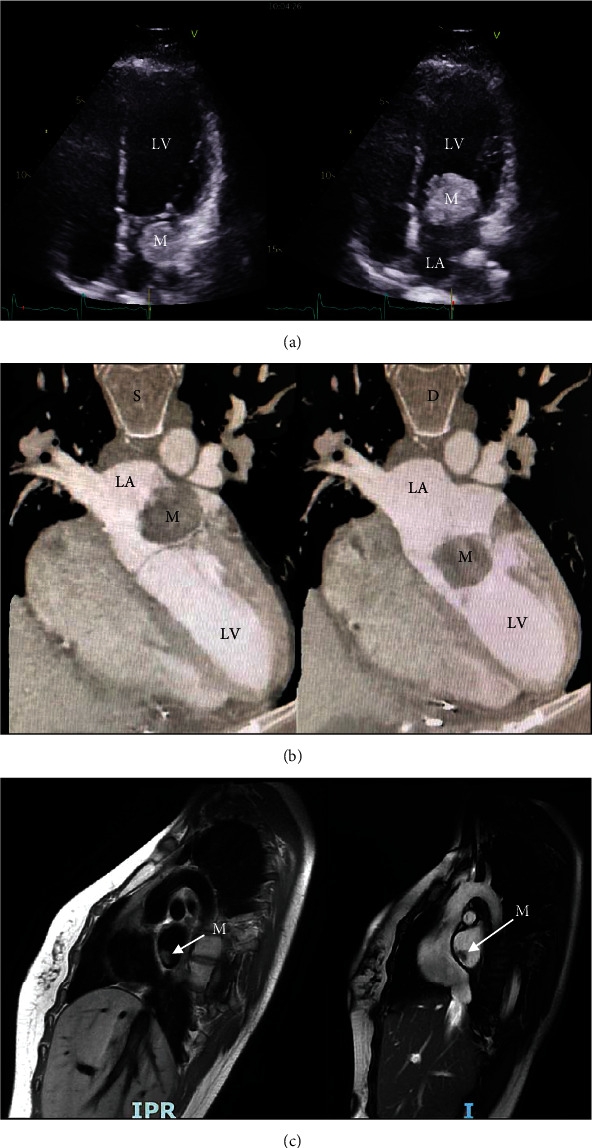

A 31-year-old female patient with a previous history of Carney complex and surgical resection for cardiac myxoma and bilateral adrenalectomy at 18 years old and 10 and 11 years old, respectively, was referred to our department with a diagnosis of recurrent biatrial myxomas incidentally discovered on echography. A magnetic resonance imaging (MRI) confirmed the diagnosis of a tumor protruding into the left ventricle, and the patient underwent a surgical resection of a large left atrial mass and a right-sided atrial small tumor. Diagnosis of bilateral atrial myxomas was confirmed by histologic studies. Postoperative outcome was uneventful, and the patient was discharged at the 7th postoperative day. Few months later, she reported trivial clinical symptoms suspecting a cervical radiculopathy. MRI confirmed the presence of a compressive cervical spinal cord tumoral mass at the C2-3 level leading to perform a surgical exeresis of the tumor. Histology showed a spinal melanotic schwannoma. This case highlights the risk of unexpected ubiquitary tumor locations and the importance of a rigorous transversal multidisciplinary follow-up to prevent severe complications in patients with Carney complex.